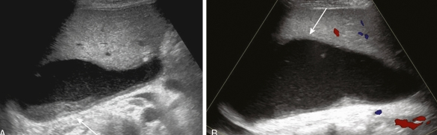

portal vein thrombosis (PVT)

portal vein stenosis (PVS)

HA to PV fistula (AVF)